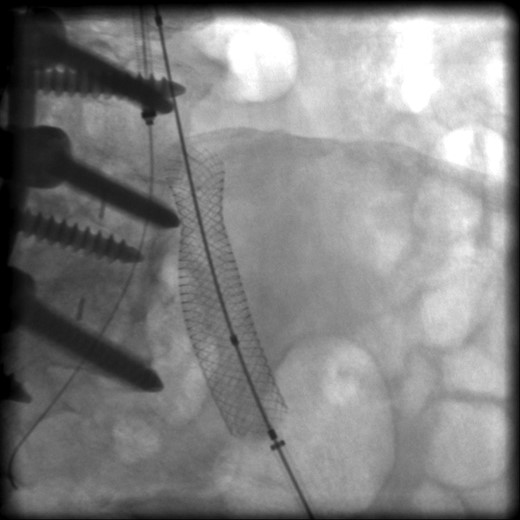

The patient was scheduled for left iliac vein stent placement. During the procedure, impingement was noted upon the posterior aspect of the vein. At this location, there was perforation of a pedicle screw through the anterior cortex of her L5 vertebral body, from prior spinal fusion. This interaction was well visualized during intraluminal inflation of a 12 mm × 40 mm high-pressure balloon (Fig. 2) and was also seen after final stent placement (Fig. 3). Because the screw tip was completely unyielding, a 14 mm × 60 mm Wallstent was used instead of the 16 mm stent we typically use, so as to avoid undue compression of her overlapping right common iliac artery. After the procedure, the patient's symptoms were greatly improved. Follow-up venography performed 4 months postoperatively showed a patent stent with slight eccentric compression at the protruding screw and no evidence of in-stent stenosis.

Perforation of a pedicle screw through the anterior cortex of L5 vertebral body visualized during intraluminal inflation of a 12 mm × 40 mm high-pressure balloon.